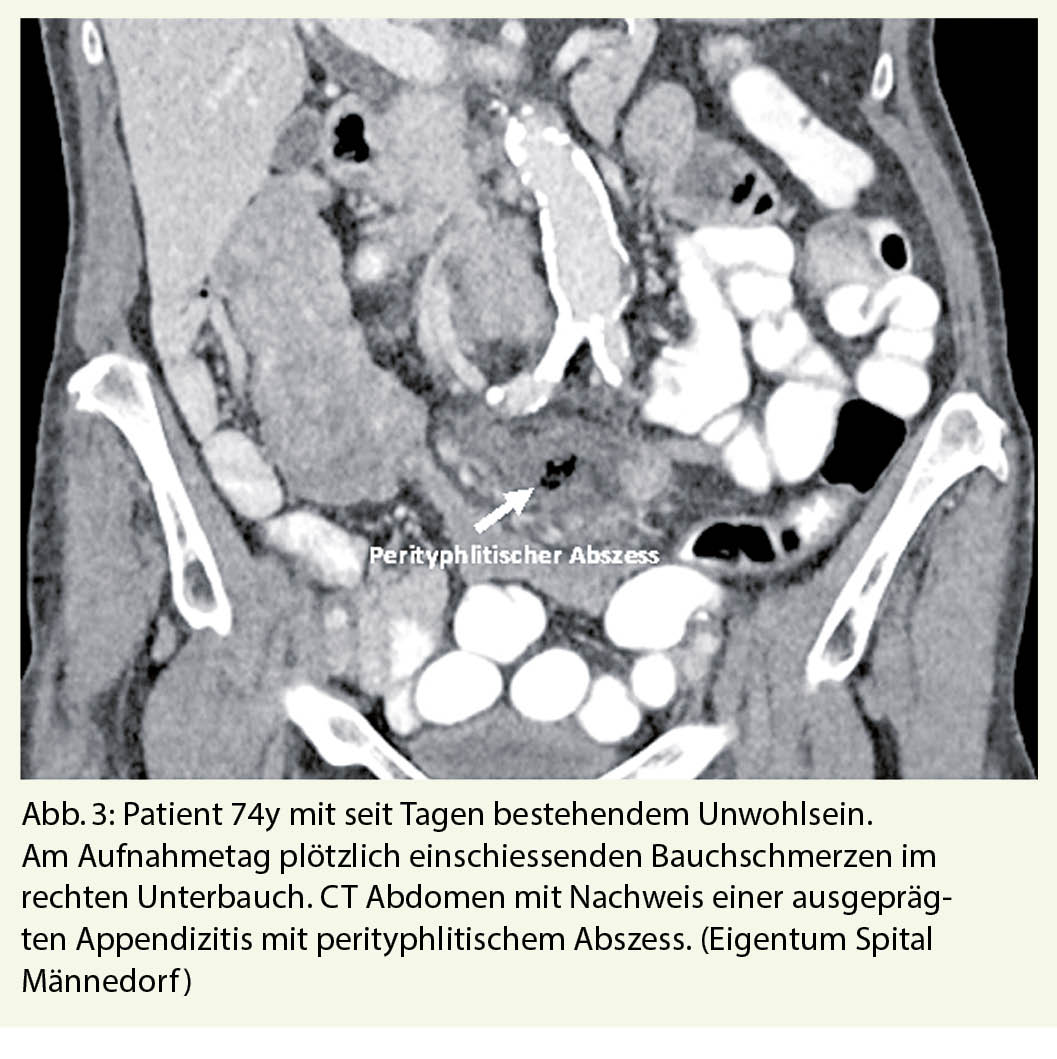

Die akute Divertikulitis des Dickdarms ist eine der häufigsten Erkrankungen, die zu einer Einweisung in den Notfall führen. Bei mehr als 50 % der über 65-Jährigen liegt eine Divertikulose vor, aus der in 10-25% eine akute Divertikulitis entstehen kann (13, 14). Auch bei einer perforierten Divertikulitis können typische Schmerzen im linken Unterbauch mit Abwehrspannung fehlen, so dass auch hier nur eine Computertomographie des Abdomens zur Klärung der Situation beiträgt. Nicht selten präsentieren sich ältere, immungeschwächte Patienten primär mit einer frei perforierten Sigmadivertikulitis, die mit einer massiven eitrigen Peritonitis und entsprechend hoher perioperativer Letalität einhergehen kann (Abb. 4)